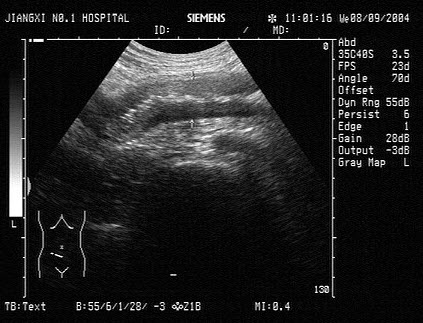

19、单项选择题

该病例最有可能诊断是()